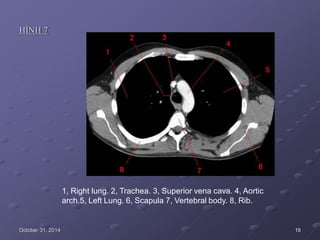

HÌNH 7

1, Right lung. 2, Trachea. 3, Superior vena cava. 4, Aortic

arch.5, Left Lung. 6, Scapula 7, Vertebral body. 8, Rib.

October 31, 2014 18